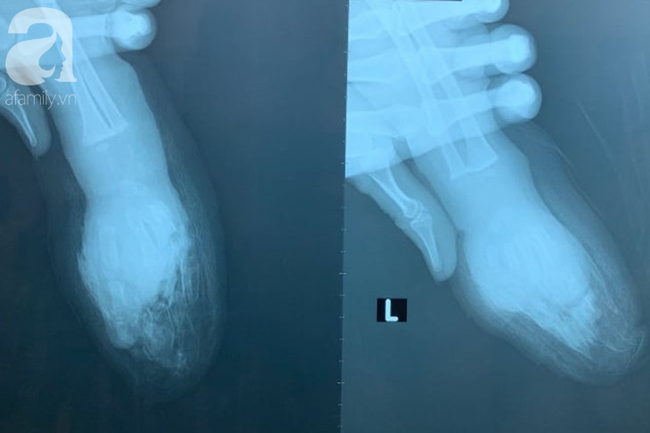

Nạn nhân là bé T.Đ.K. (1 tuổi, quê Đồng Tháp) được chuyển từ một bệnh viện chuyên khoa nhi ở TP.HCM trong tình trạng ngón 2, 3, 4, 5 tay trái bị đứt lìa, bàn tay trái bị đứt ngang ở giữa, đứt lìa đốt ngón trỏ bàn tay phải, đã được sơ cứu.

Ảnh chụp phim 2 bên bàn tay bé.